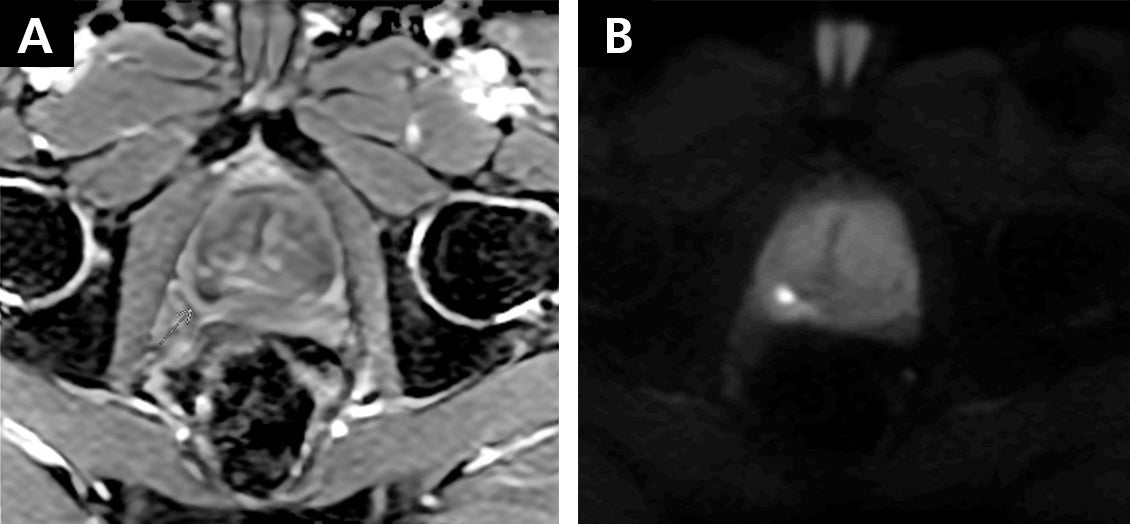

RDC diffusion with PIQE, matrix 288x288. (A) shows the ADC map and (B) is the DWI. images/ courtesy SDMI

The imaging center is appreciating dramatically enhanced diffusion weighted imaging (DWI) with Canon in comparison to other vendors’ technology due to a number of system capabilities, including an improved gradient design, Reverse Encoding Distortion Correction, and zoom DWI features.

“We can use Zoom DWI to just focus on that small field of view and get rid of the artifactual distortions that would occur if you were using a larger field of view. It’s not just one element—it’s the magnet, the gradient, the distortion correction, the zoom features. All these together produce a good clinical result,” Dr. Winkler says.